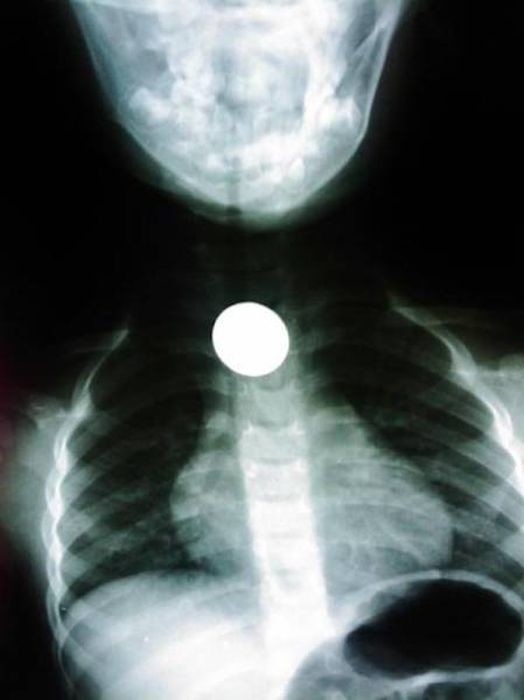

Предметы, которые не очень хочется видеть внутри себя

Под рентгеновскими лучами порой видны не только внутренние органы и кости, но и инородные тела, попавшие в организм

Истории попадания этих предметов в организм могут быть самыми невероятными и запутанными, но больше всего медиков интересует процесс их извлечения, впрочем, в этом заинтересованы и сами пациенты, допустившие нечто подобное со своим телом.